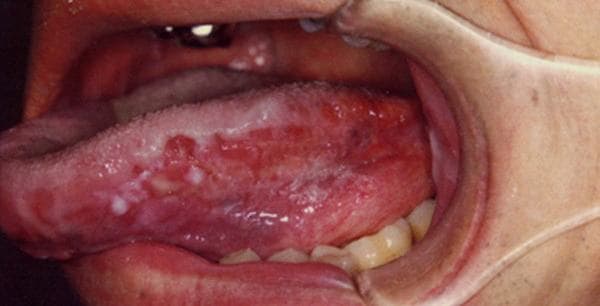

Hình ảnh ung thư lưỡi giai đoạn đầu thường chỉ là những vết loét hay nhiệt trên lưỡi nên nhiều người bỏ qua, cứ nghĩ vài ngày sẽ khỏi.

Với ung thư lưỡi, các vết loét hay nhiệt miệng này sẽ kéo dài trong thời gian dài, không khỏi. Vết loét lớn dần và có thể lan ra ngoài lưỡi đến môi hoặc vòm họng, gây đau đớn khó chịu. Khi quan sát kỹ sẽ thấy có mủ hoặc chảy máu ở vết loét.